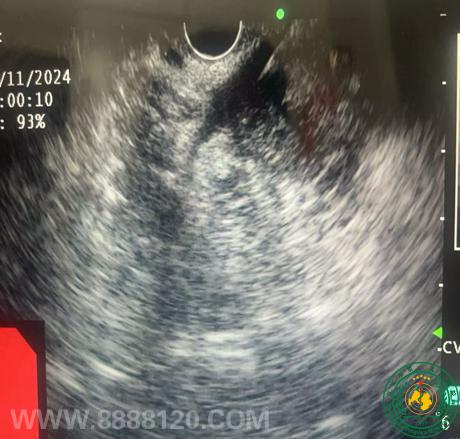

宜宾市首例 经超声内镜引导下胆囊细针穿刺活检术

宜宾市首例 经超声内镜引导下胆囊细针穿刺活检术58272

宜宾市第二人民医院 图文